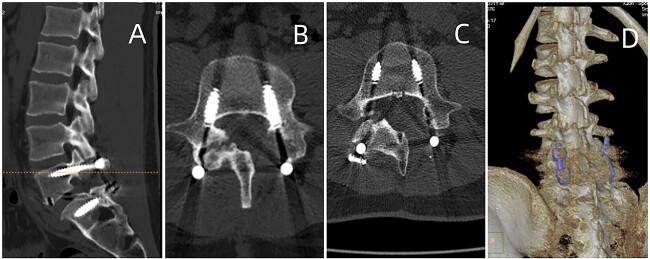

Spinal gout is a rare occurrence, and the combination of gout with lumbar spondylolysis has not been reported. We present a unique case involving a 29-year-old male who complained of low back pain for 1 month. Computed tomography and magnetic resonance imaging revealed articular subchondral erosions and a mass in the left L5-S1 facet joints. Initially treated for a spinal infection, the patient subsequently underwent lumbar spinal canal decompression and fusion, achieving complete relief. Postoperative pathology confirmed the spinal lesions to be tophaceous gout. Dual-energy CT or biopsy can assist in confirming the diagnosis. This report discusses another rare case of tophaceous gouty arthritis with spondylolysis to be added to the literature.

脊柱痛风较为罕见,痛风合并腰椎峡部裂的情况尚未见报道。我们报告一例独特病例,患者为一名29岁男性,主诉下腰痛1个月。计算机断层扫描和磁共振成像显示左L5-S1小关节软骨下侵蚀及肿块。患者最初按脊柱感染进行治疗,随后接受了腰椎管减压融合术,疼痛完全缓解。术后病理证实脊柱病变为痛风石性痛风。双能CT或活检有助于确诊。本报告讨论了另一例罕见的痛风石性痛风性关节炎合并峡部裂病例,以丰富文献资料。